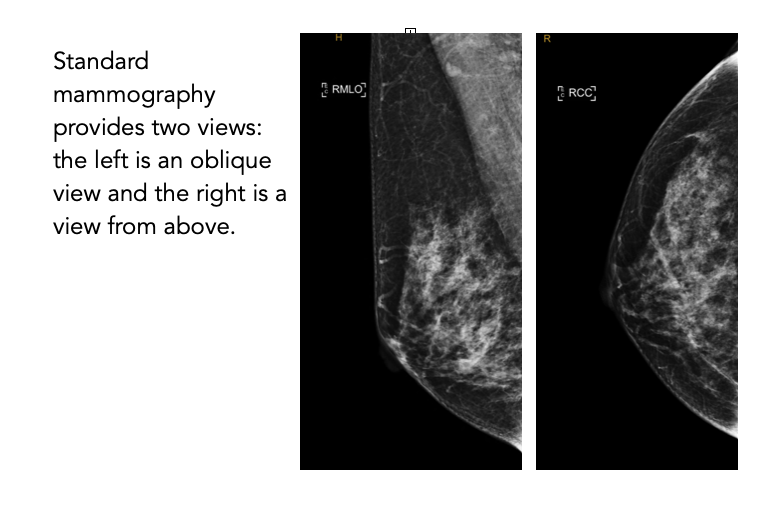

A low-dose X-ray specifically designed to image the breast tissue. It is the most common imaging tool used for routine breast screening.

During a mammogram, the breast is compressed between two plates to obtain clear X-ray images. The procedure typically takes 15–30 minutes. Some patients may feel temporary discomfort during compression.